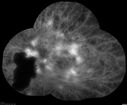

Pregnant - 25 weeks - new onset PDR and DME both eyes - Treated with PRP and ozurdex294 views29 year old female. Patient is 25 weeks pregnant and having flare up of retinopathy in both eyes. She states it is worse in the left. Patient has trouble with distant vision. At most recent visit, 1 years ago, VA was 20/20 OU. Two years ago anterior uveitis x 1 episode with normal labs (HLAB27, FTA, ACE, Lyme). 2017-2020 – Lucentis for DME left eye only.

PMHx: Type I DM since teenager, hyperlipidemia

BP was normalOct 19, 2021